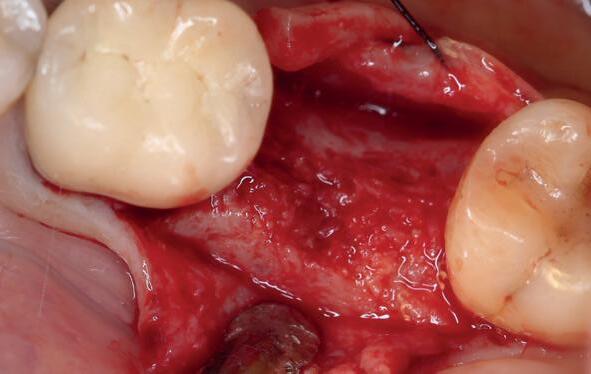

Zes maanden na extractie wordt het implantaat 37 geplaatst. Er is sprake van een goede genezing en de processushoogte en -breedte zijn behouden en opgebouwd. Ook is er zichtbaar gekeratiniseerd weefsel

1 2 Ridge preservation met d-PTFE membranen 35

gewonnen. De wond kan na het plaatsen van een healing abutment primair gesloten worden (Afbeelding 3a-3d).

In afbeeldingen 4a-c is het resultaat drie maanden na het plaatsen van het implantaat te zien. De genezing is volledig en de verwijzer kan de suprastructuur vervaardigen (afbeelding 4a-4c).